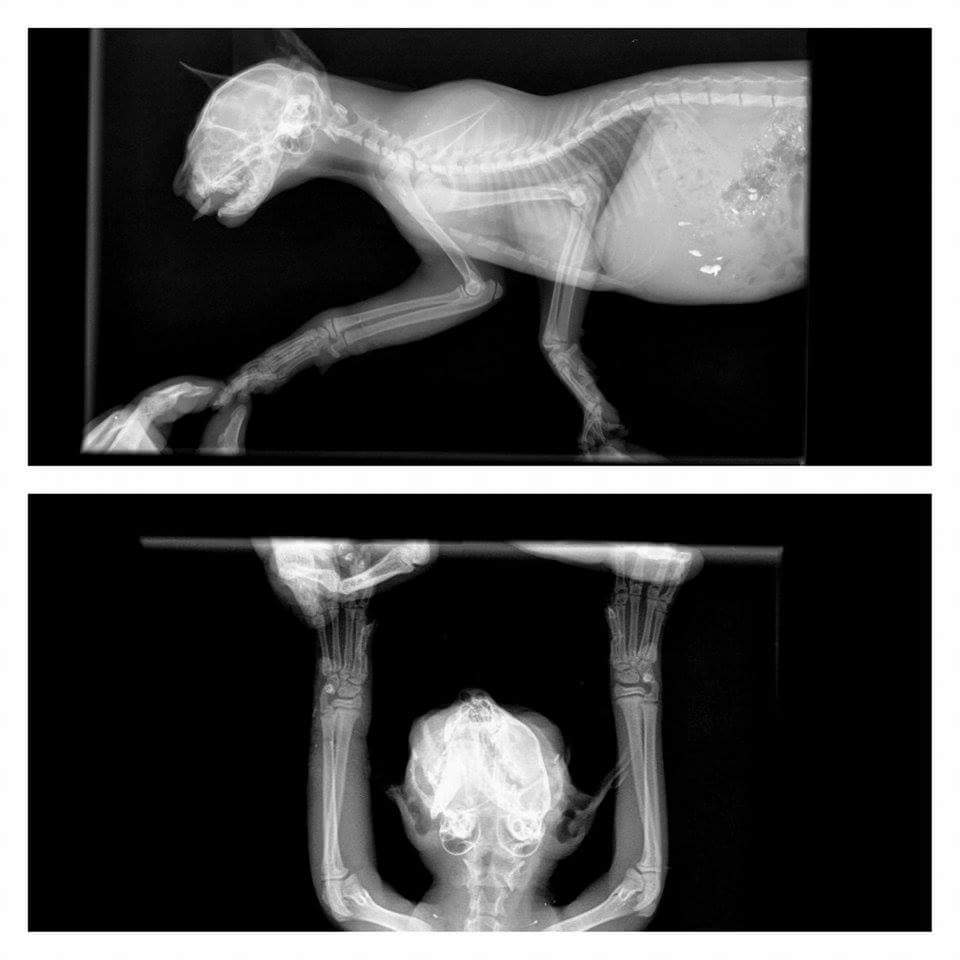

主題: 慘遭捕獸夾夾傷的可憐小小貓 申請者姓名: 劉晏 花色: 申請日期: 2015-10-27 05:21:37 申請者部落格: 申請者臉書網址: https://www.facebook.com/profile.php?id=100008167170200&__nodl 所在縣市/合作醫院: 高雄市/弘恩動物醫院 治療費用: 7400元 需求人數: 18人 已結案 (2023-01-18 23:37:41) 報名人員: Kitty Chen(已付款)、姿鈴(已付款)、蘇艾倫 x4(已付款)、Candyfloss Hi(已付款)、Tina Tseng x2(已付款)、懶羊羊 x2(已付款)、Kelly Chien(已付款)、蘇小優 x4(已付款)、JO(已付款)、徐小安(已付款)、 候補人員: 動物病情說明: 小小貓是跟著媽媽最近剛出現我的餵養區的貓,還在跟貓媽媽培養感情中,不料∼前天清晨餵食時,遠遠就聽到貓咪的哀嚎聲,本以為是貓咪間的打架,但是映入眼簾的卻是怵目驚心的畫面,ㄧ隻不到兩個月的小小貓死命得似乎想要掙脫某個東西,而發出喀∼喀∼的聲響,向前ㄧ看....竟然是捕獸夾,天ㄚ!!我當時真的嚇壞了,小貓又因為疼痛和恐懼,ㄧ直對我嘶吼!!!

貓媽媽也因此嚇的只敢站在遠處看,當下緊急,所以隨手抓了鄰居的床單包裹,趕緊請家人幫忙解開捕獸夾,天亮後趕快送醫...

10/18醫院初步診斷:左前肢捕獸夾夾傷,傷口腫脹有細菌感染敗血症的現象,脫水,氯離子過高須校正,還須觀察是否有併發症,先行針劑及點滴治療,因為送醫送得快,所以截肢可能性不高,待後續觀察治療

10/20前往探視小小貓,精神不太好,吃得很少,醫院表示,今天有發燒,所以精神較不好,這是細菌感染的普遍現象,會反覆發燒,眼睛感染部份也有給予點藥,剛好醫院要檢查傷口,看起來還不錯,沒有惡化的跡象,希望小小貓要加油,努力撐過過度期......

10/22買了ㄧ些幼貓罐來給小柑橘吃,醫院說狀況有穩定,腳傷有消腫,沒再發燒了,可自己進食,已拆掉點滴觀察,沒問題..後天就可出院了!!